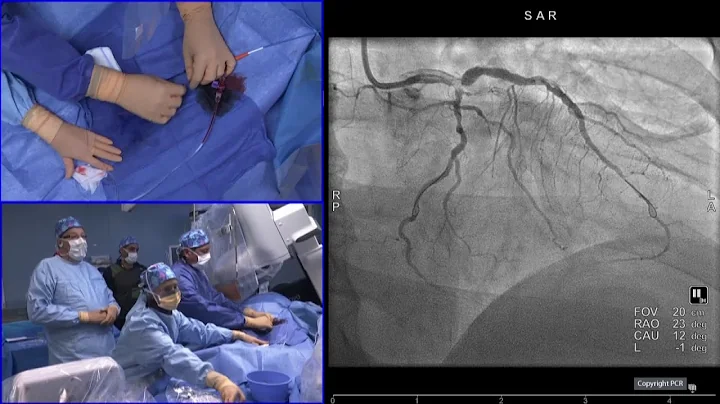

Drugs And Devices Synergy: Optimal Dapt & Switching Strategies - Round Table Webinar

In this special webinar about drugs and device synergy Thomas Cuisset leads the discussion with Adrian Banning and Olivier ...